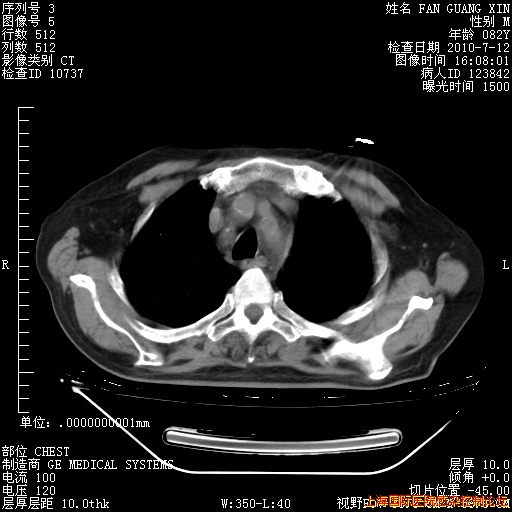

6月12日纵膈窗